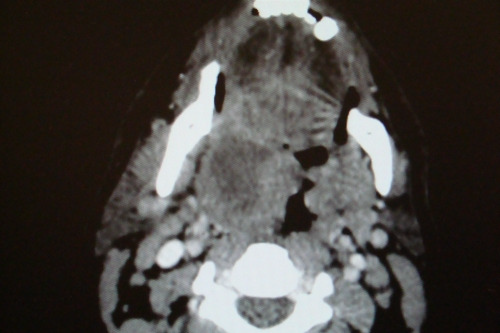

INSTRUÇÃO: Analise a imagem a seguir para responder à questão 07:

Disponível em: <http://bancodeimagensorl.com.br/2017/01/13>. Acesso em: 2 set. 2019.

Paciente masculino, 20 anos, dá entrada no pronto-socorro, relatando odinofagia unilateral intensa, com irradiação para orelha ipsilateral, febre 39 graus, limitação à abertura bucal, voz anasalada, mas eupneico, estado geral preservado, pulsos cheios e simétricos, normotenso. Quadro com cinco dias de evolução e está em D4 de amoxicilina. Apresenta a tomografia acima.

Sobre esse relato, podemos afirmar: